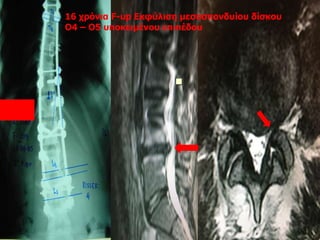

16 χρόνια F-up Εκφύλιση μεσοσπονδυίου δίσκου

Ο4 – Ο5 υποκειμένου επιπέδου